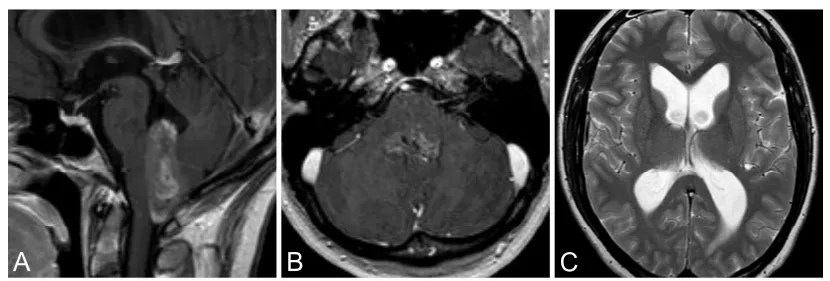

32岁娜娜,因头痛、眩晕及间歇性瞳孔不等大就诊。MRI示第四脑室均匀强化占位并梗阻性脑积水(图2A–C)。

术中在神经电生理监测下全切肿瘤。术后出现短暂右侧外展神经麻(约数日),以及右侧舌咽、舌下神经麻(约两周),均完全恢复。

术后即刻MRI未见肿瘤残留,术后32个月随访MRI未见肿瘤复发及脑积水征象(图2D–F)。